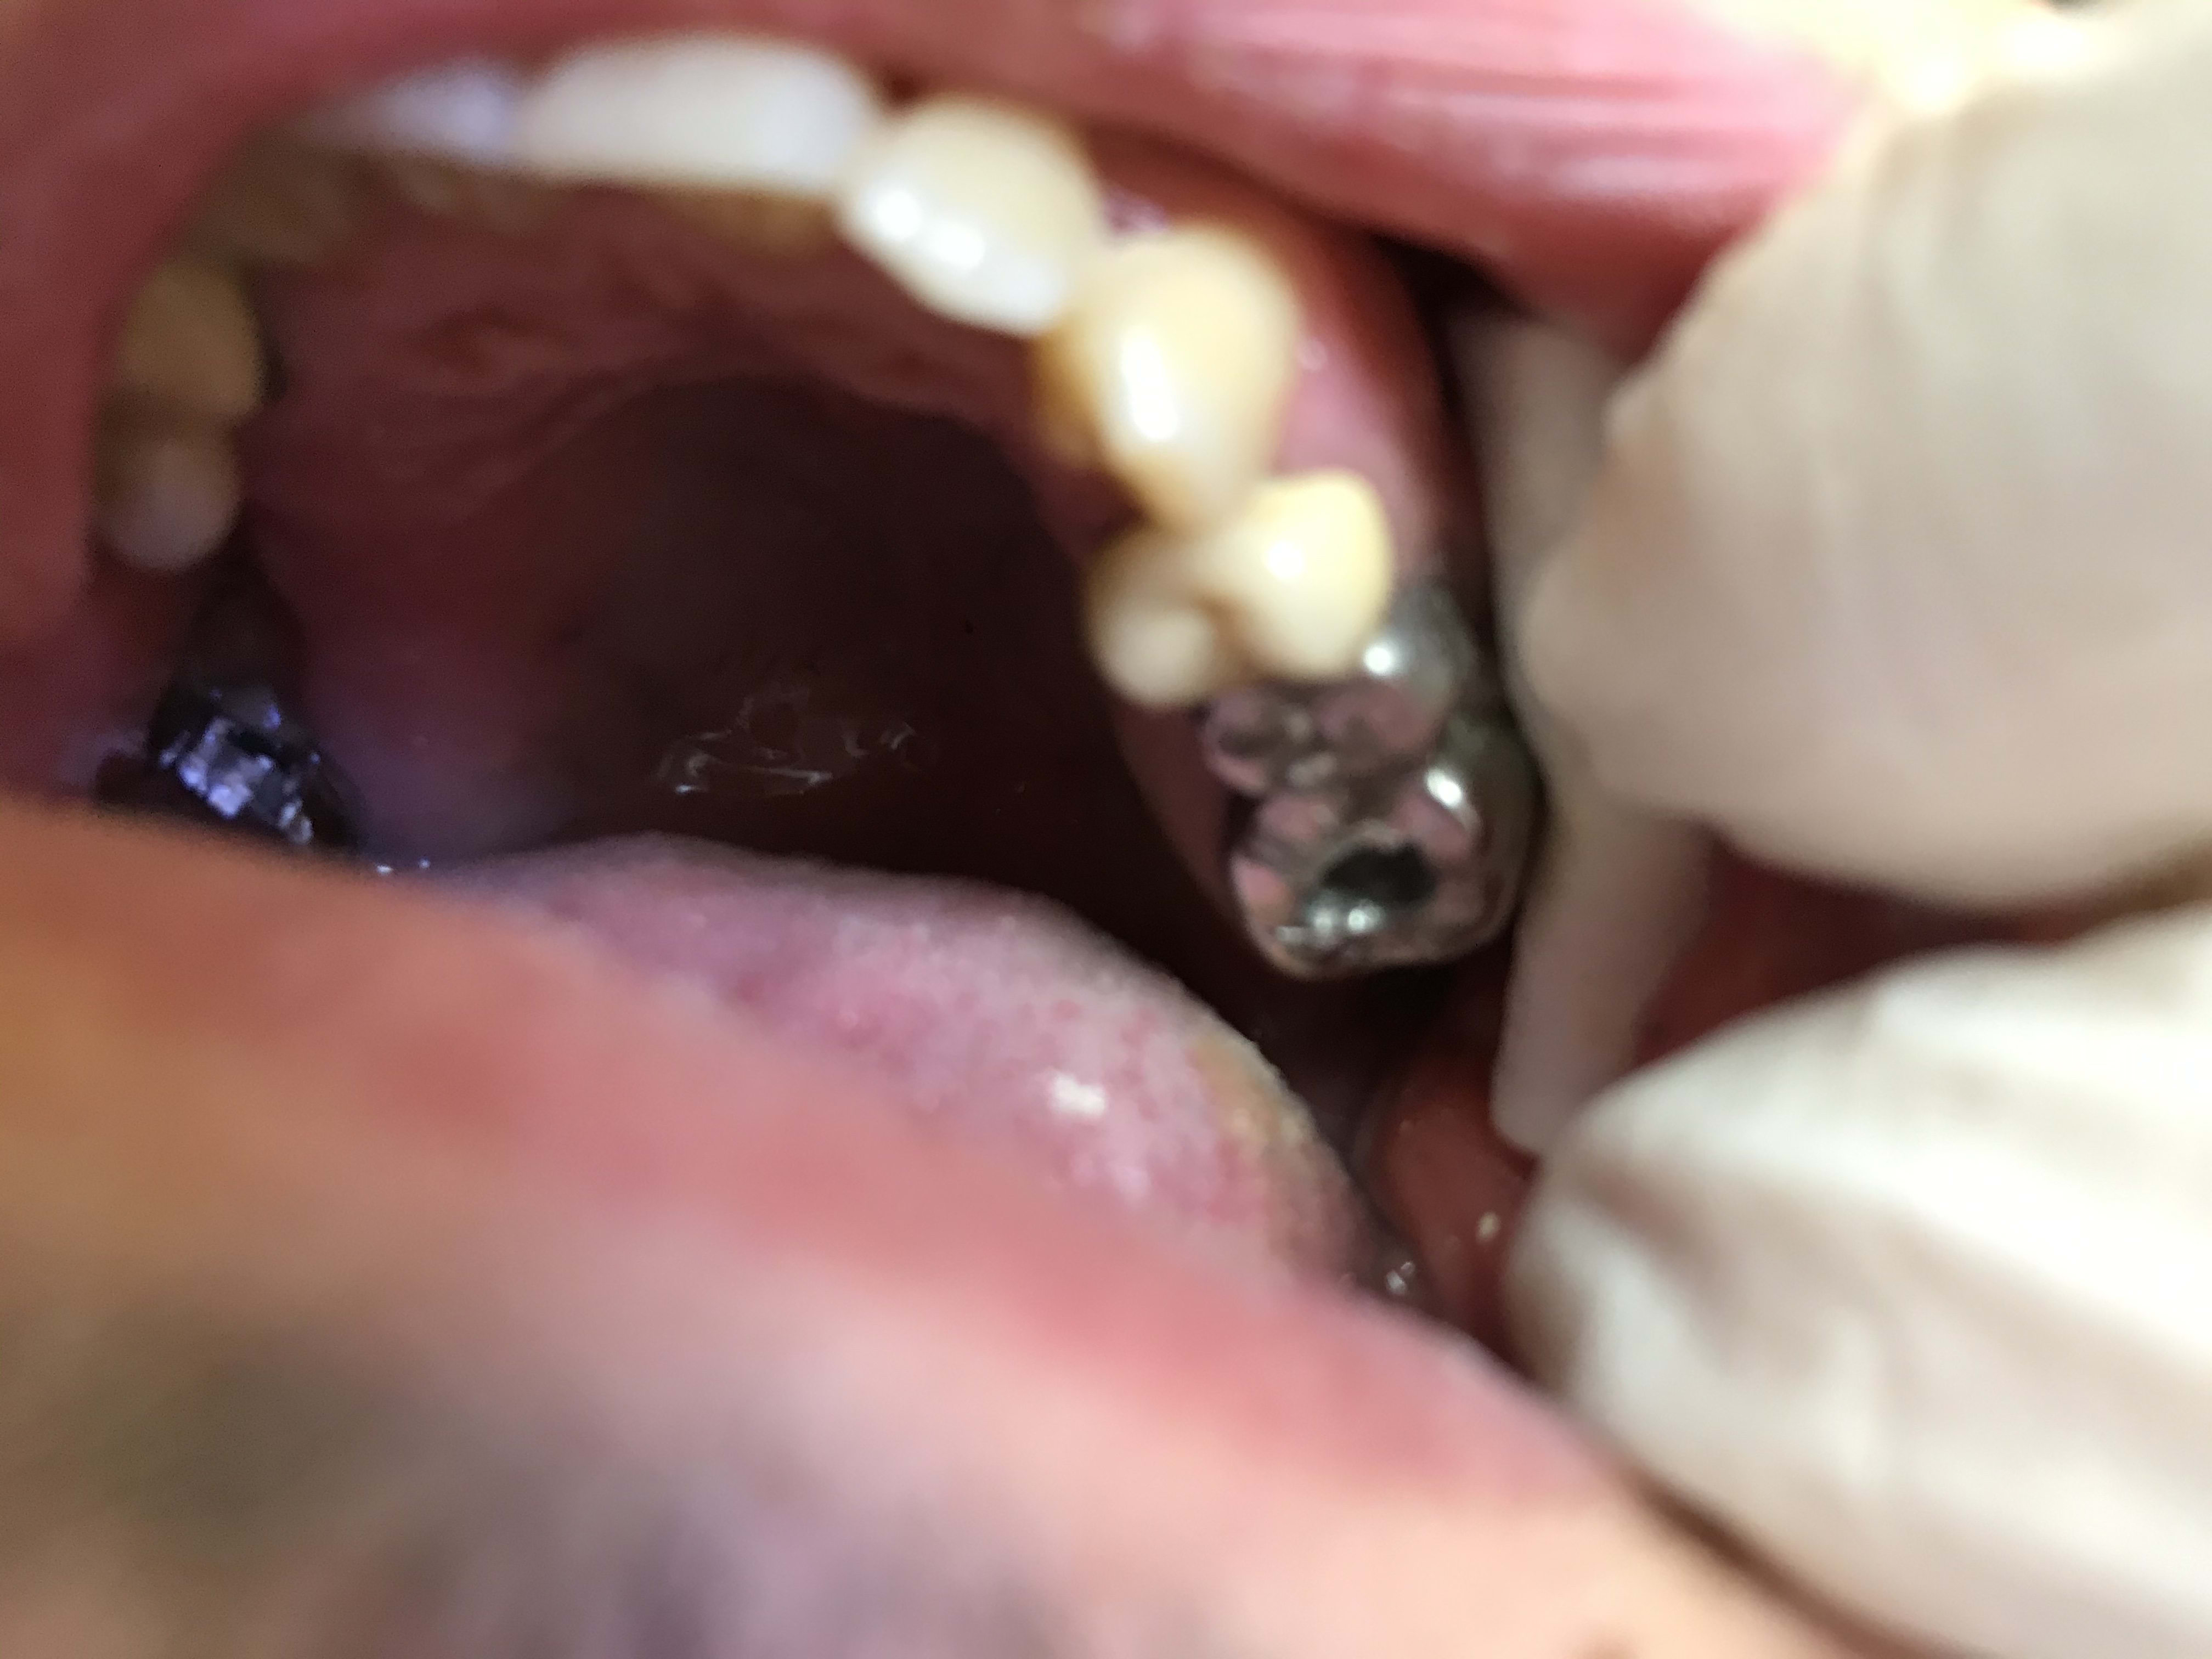

Vous avez une 6 en CC , il y a un traitement endo à faire , vous faites le trou l’endo .... par quoi rebouchez vous le trou ensuite ? Quel matériau ?

lemondestvaste

24/10/2019 à 17h16

J achète une boîte d amg juste pour ça 😂😂😂

Une boite d'AMG en urgence ? voila voila ….

Justement les composites ne collent pas au métal d’une CC ou au CCM .... par conséquent l’obturation ne doit pas être réalisée en composite mais en amalgame :))))) allez bim remballez vos composites de merde :) un bon amalgame fourré au doigt , y a que ça de vrai :) Et en plus c’est de la même teinte que le métal de la couronne coulée .